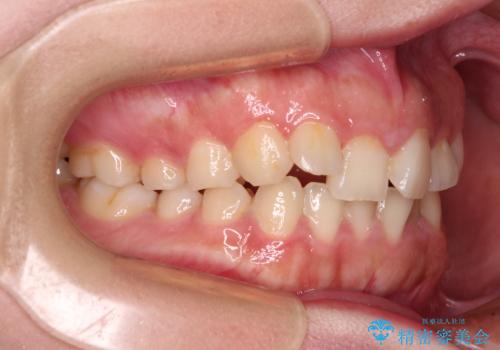

捻れて前に出ている前歯 ワイヤー装置での非抜歯矯正

- 捻れて前に出ている上顎前歯と全体的なデコボコを気にして来院された患者様です。

口元の突出感は強くなかったため非抜歯矯正での対応となりますが、捻転を改善する際に上顎前歯が前突する可能性があったため、上顎臼歯部にアンカースクリューを使用して、歯列が前方に転位しないようにすることとしました。

ワイヤー矯正でもインビザラインでも対応可能でしたが、上顎歯列が前方位であるときには、ワイヤー矯正の方がより良い仕上がりとなる可能性が高いため、ワイヤー矯正をおすすめいたしました。